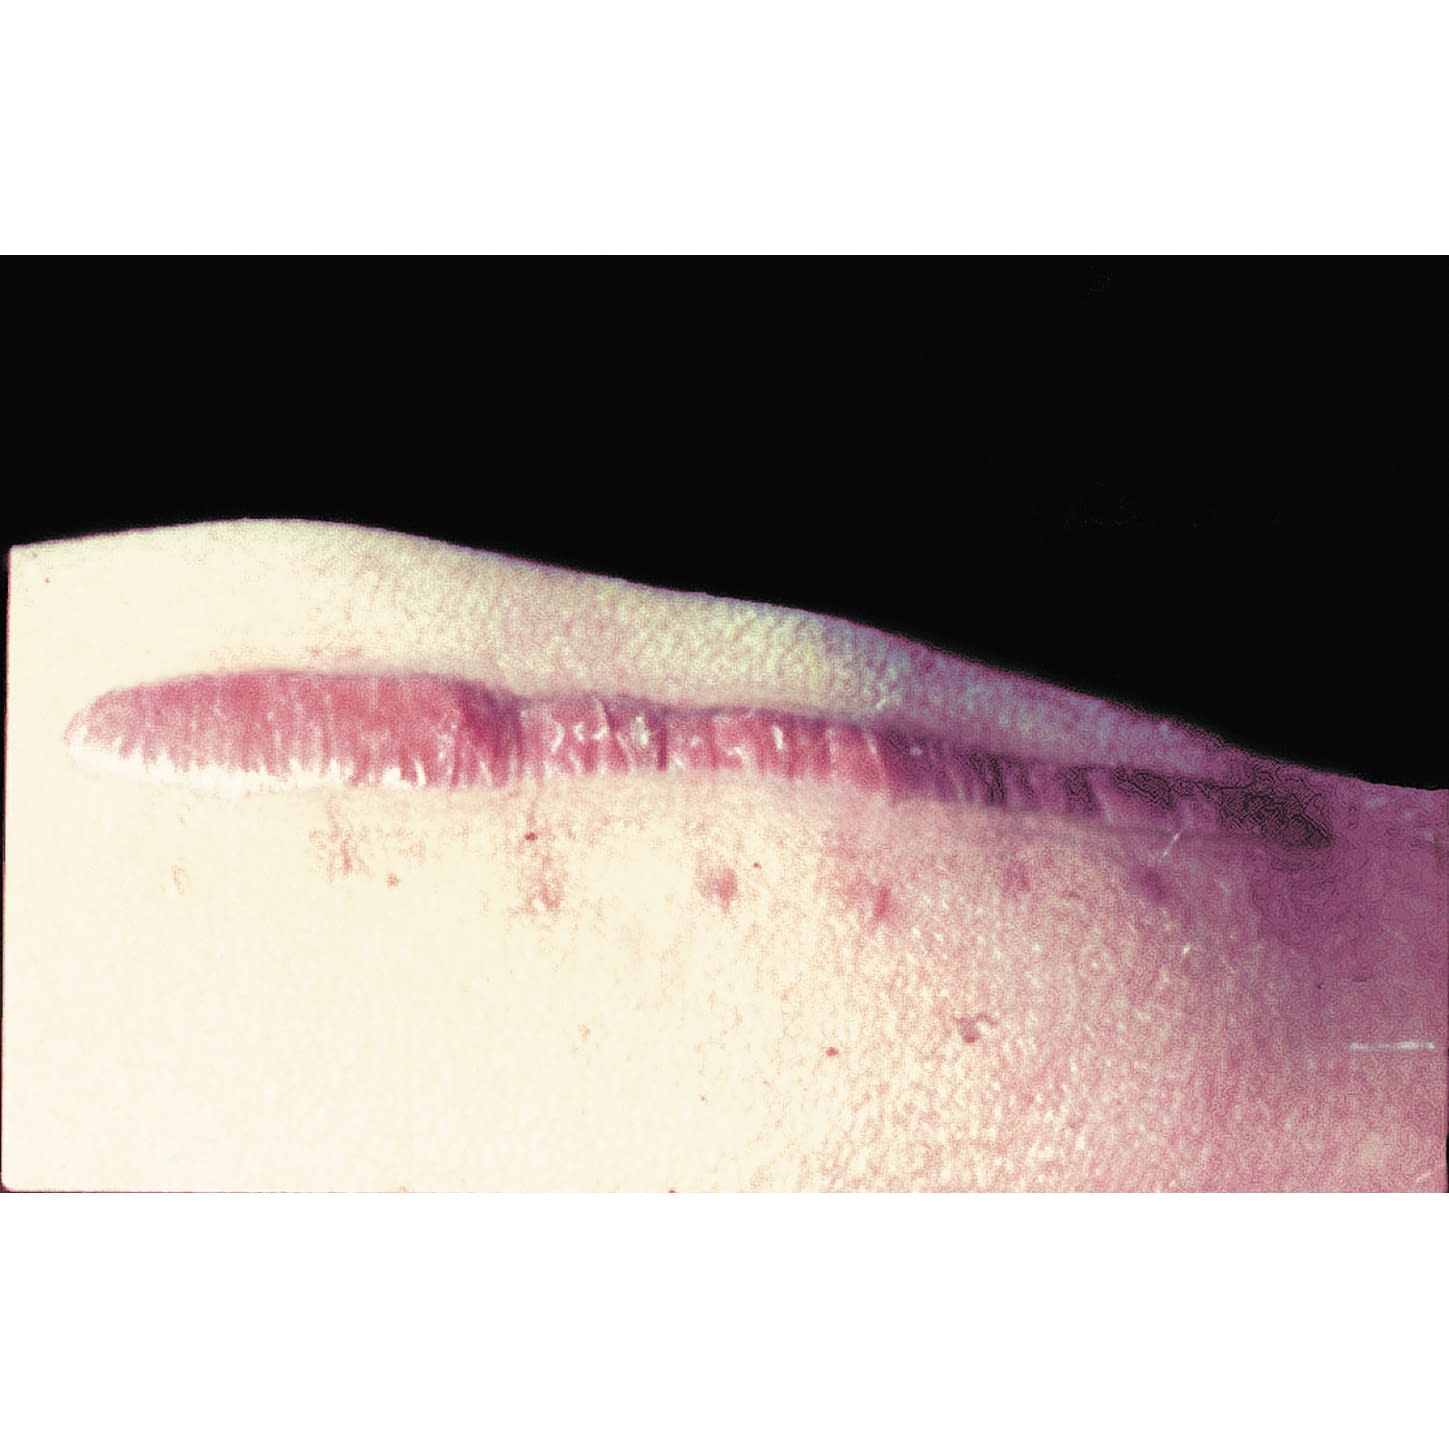

皮膚を保護する粘着性シリコンジェルシート

●皮膚にやさしいセーフタックテクノロジーを採用。表皮剥離や皮膚損傷が起こりにくいシリコンジェルシートです。●固定力が高く、テープなどで固定する必要はありません。●薄くて柔らかく、肌色なので目立ちません。●1枚ずつ包装されていますので衛生的です。●EOG滅菌済。